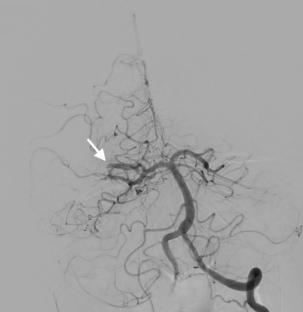

在经循环取栓术中,交通动脉通过后循环进入前循环,反之亦然。由于复杂的血管解剖结构或涉及颅外和颅内血管的慢性病变,传统的顺行血管内入路具有挑战性,该入路可用于患者。到目前为止,只有几篇文章讨论了这种方法。在这里,我们提出一个68岁的妇女谁提出了突然发作的左侧无力的情况下。CT血管造影显示右侧颈总动脉(CCA)闭塞,同侧大脑中动脉(MCA) M1段闭塞。通过后交通动脉(Pcomm)通畅,采用经循环入路对右MCA闭塞进行了成功的栓塞切除术。出院时,患者有轻度缺陷,随访1个月后完全恢复。我们的病例强调了这种技术的有效性和安全性,尽管有潜在的并发症,如延长手术时间。需要进一步的研究来优化患者选择和技术。

In a transcirculation thrombectomy, the communicating arteries are used to access the anterior circulation via the posterior circulation, or vice versa. This approach can be used in patients where traditional anterograde endovascular approaches are challenging due to complex vascular anatomy or chronic lesions involving extracranial and intracranial vessels. Up until now only a few articles addressed this approach. Here, we present a case of a 68-year-old woman who presented with a sudden-onset left-sided weakness. CT angiography showed an occlusion of the common carotid artery (CCA) on the right side and an ipsilateral occlusion in the M1 segment of the middle cerebral artery (MCA). A transcirculation approach was used to perform a successful embolectomy for the right MCA occlusion through the patent posterior communicating artery (Pcomm). At discharge, the patient had mild deficits and fully recovered at 1-month follow-up. Our case highlights the effectiveness and safety of this technique, despite potential complications like prolonged procedure time. Further research is needed to optimize patient selection and technique.